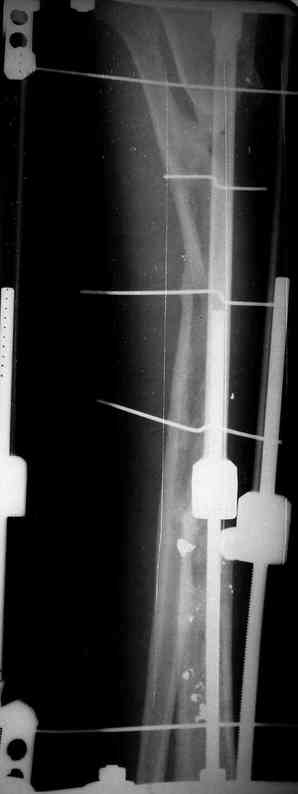

5. Ну и чтобы не быть голословным. Молодой человек подорвался на фугасе (Чечня, 2005 год). Свежие рентгенограммы:

Соответственно ожоги и дефект мягких тканей, переломы костей стопы и пр. Наложили аппарат

Илизарова (как придется), хирургически обработали и героически заживляли мягкие ткани с многочисленными кожными пластиками. В итоге через полгода я принял его вот таким:

Рентген в процессе перемещения - внизу карбоновые кольца, тракция фрагмента спицами с упором.